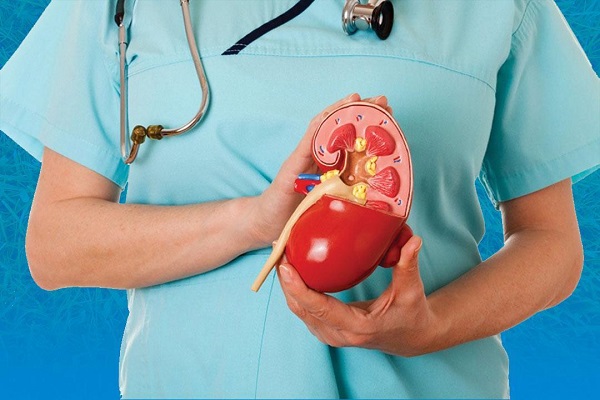

- نائب وزير الصحة يجري جولة مفاجئة لمستشفيي التأمين الصحي والصدر بالمنيا